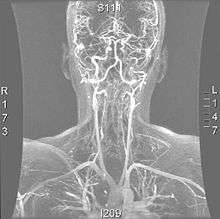

- Magnetic resonance imaging (MRI)

Magnetic resonance imaging has the ability to quantify the plaque anatomy and composition. This allows physicians to determine certain characteristics of the plaque such as how likely it is to break away from the wall and become an embolus. MRI does not use ionizing radiation, so the number of times that it is used on a single person is not a concern; however since it uses strong electric fields those who have metal implants in cannot use this technique.[1][2]